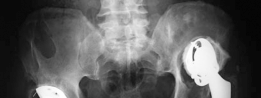

Can you describe the radiograph? This is an AP radiograph of the right hip. There is a pathological fracture …